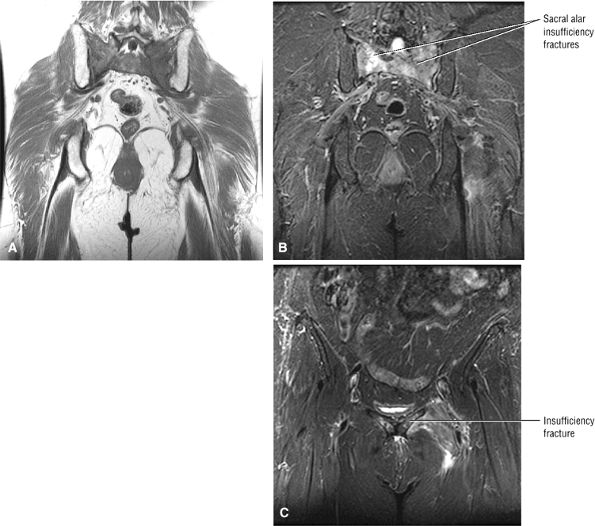

FIGURE 3.28 ● Normal coronal anatomy of the hip. (A, B) In the setting of pubic rami fractures, the sacrum and sacroiliac joints should be examined for the presence of fractures or a diastasis completing the pelvic ring fracture. (C, D) Sacral insufficiency fractures or sacroiliitis is seen only on images with a large field of view. Occasionally they are the only significant finding in a patient with unilateral hip pain. (E, F) Images with a large field of view should also be used to examine the pelvic viscera, especially in women, for adenopathy, masses, and adnexal or uterine pathology. (G, H) Articular cartilage covering the acetabulum and femoral head is clearly displayed. A small portion of the medial femoral head (the fovea) and a large portion of the medial acetabulum (the acetabular fossa) are devoid of cartilage. (I, J) Early signs of degenerative arthrosis may be seen in the anterior superior quadrant of the hip, including cartilage thinning and fraying, subchondral edema in the anterosuperior acetabulum, and anterosuperior labral tearing. (K, L) The anterior superior portions of the bilateral acetabuli are visualized on images obtained with a large field of view. These images allow appreciation of subtle differences in symmetry of the acetabular contour. Even mild acetabular dysplasia may be accompanied by unilateral labral tears and chondral degeneration. (M, N) Osseous spurring at the symphysis pubis is a common finding. Occasionally, acute or insufficiency fractures occur immediately to the left or right of the symphysis pubis, and are seen only on images obtained with a large field of view.